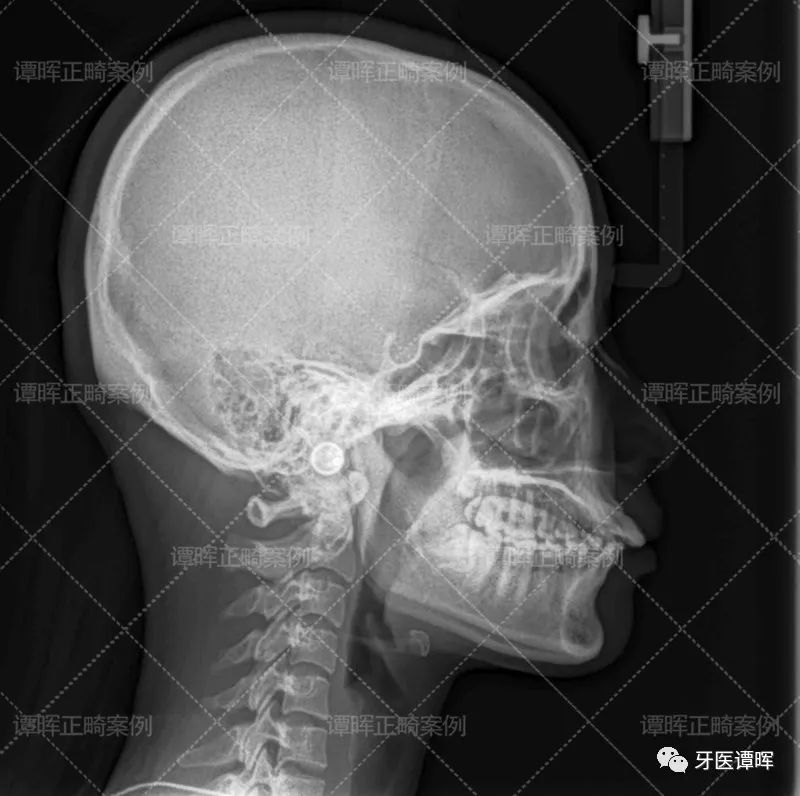

△X线分析:明显看出前牙往前突,上牙的侧切牙也是非常不齐。

俗话说:再漂亮的嘴唇遇到乱乱的一口牙也是一秒拉下神坛。因为前牙往外突,侧牙又往内收,中间门牙小,所以,前牙会显得有点大。如果开口说话,就会显得很不协调!